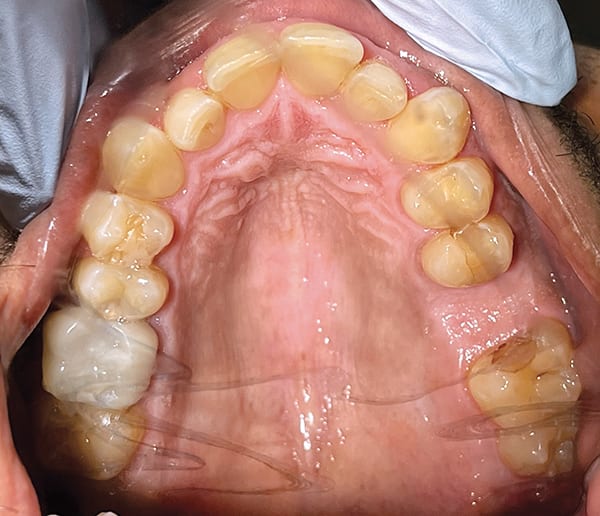

A 27-year-old male patient presented with severe crowding, misaligned teeth, difficulty in maintaining proper cleaning and flossing, crossbites of mandibular canines, dark vestibule appearance, and displeasure at his overall smile and appearance. The clinician specifically selected ClearCorrect® aligners (Straumann, clearcorrect.com), a Straumann Group brand renowned for its thermoplastic rigidity and high trimline design, due to their ability to effectively meet the retention requirements of this case. The Unlimited case type was selected, which is ideal for comprehensive treatment, long-term retention, and minimizing unexpected expenses. Optimal results were achieved with the expansion of the buccal corridor and by placing occlusal bite ramps to open the bite and correct the anterior crossbite. For proper space maintenance, a bar was placed on tooth No. 19. The patient's total treatment plan included two phases: (1) 16 steps in 6 months that included the extraction of teeth Nos. 1, 16, 17, and 32, expansion of the buccal corridor, and placement of engagers on teeth Nos. 6, 7, 10, and 20; and (2) 18 steps completed over 9 months. Upon completion of treatment, crossbite issues were resolved, overall general oral health was improved, and the patient was pleased with the results. Full-time ClearCorrect retainers were created for both the maxillary and mandibular arches to be worn thereafter.